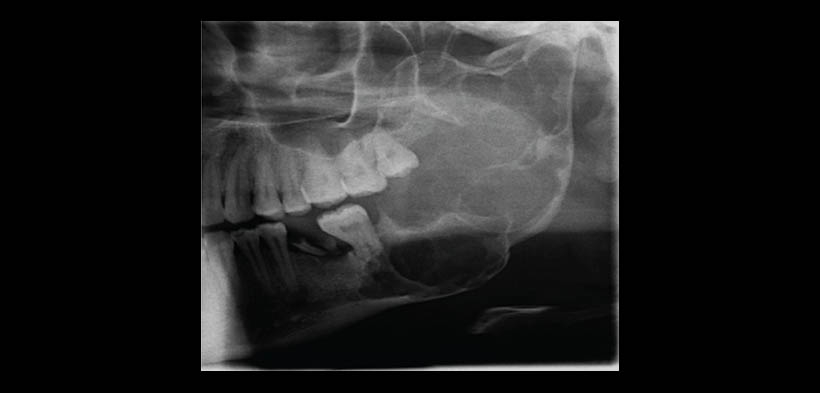

Es bien sabido que ameloblastoma se evidencia radiológicamente como una lesión radiolúcida unilocular o multilocular ( apariencia de burbujas de jabón). Radiológicamente, las lesiones son expansivas, con adelgazamiento de la corteza en el plano bucal y lingual. En ocasiones, las radiografías convencionales revelan ameloblastomas uniloculares, asemejándose a quistes dentígeros o el tumor queratoquistico. La apariencia radiográfica del ameloblastoma puede variar según el tipo de tumor. La tomografía computarizada (CT) es generalmente útil en la determinación de los contornos de la lesión, su contenido, y su extensión a los tejidos blandos.

Los hallazgos inusuales de la TC pueden evidenciarse en aquellas lesiones de gran crecimiento y larga data que pueden causar desfiguración de las estructuras circundantes debido a la presión, sin la necesidad de invadir dichas estructuras. Arora, et al realizaron un reporte de caso de un ameloblastoma pleximorme localizada en el cuerpo ángulo y rama mandibular izquierdo, y cuyo crecimiento produjo la deformación de la hemimaxila de dicho lado, considerándose a este hallazgo como algo inusual (fig.1-4)(1).

Fig. 1. Radiografía panorámica, muestra una lesión osteolitica bien delimitada localizada en el cuero, ángulo y rama mandibular izquierdo, se evidencia deformación de la apófisis coronoides.